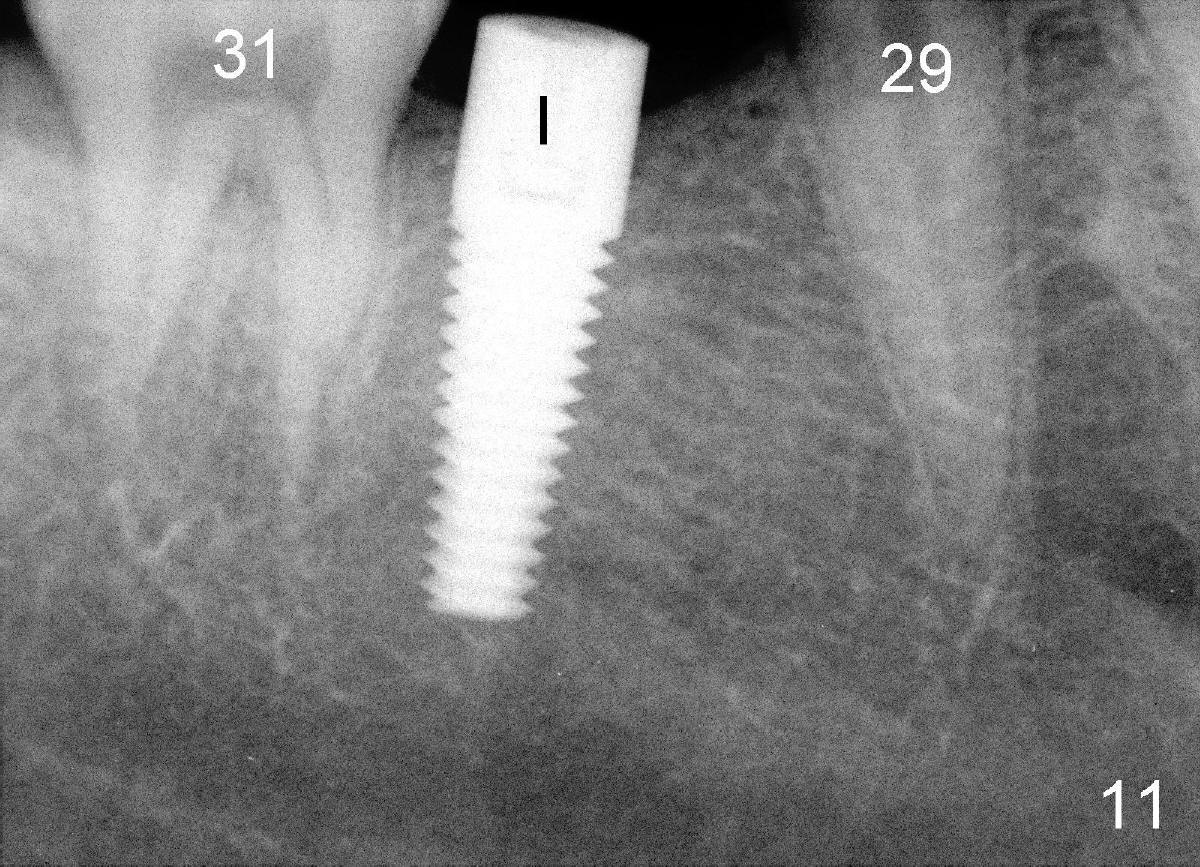

Twenty-year-old man requests restoring missing tooth #30 (Fig.1), but the edentulous space (red lines) is narrow as compared to the mesiodistal width of #19. Ideal treatment plan is to distalize #31 (red arrow) with mini-implant (mini in short) and restore the missing tooth with traditional implant.

The tooth #31 is uprighted in six months (Fig.8, as compared to Fig.5). The edentulous space increases from 6 mm to 9 mm mesiodistally, which is still not enough. The M-D width of #19 is 12 mm. In fact, the tooth #2 has been intruded substantially (Fig.9. Compare to Fig.3). The possible reason for resistance of distal movement of #31 is an interference from the tooth #3 (Fig.10). A regular implant is placed intentionally in the distal aspect of the edentulous area (Fig.11: I). The next plan is to place temporary crown on the implant once it osteointegrates to raise the occlusion efficiently so that the tooth #31 is free to move distally with retraction of power chain attached to the mini-implant (as shown in Fig.2). The regular implant may be also used as anchorage to push #31 distally. See you later.